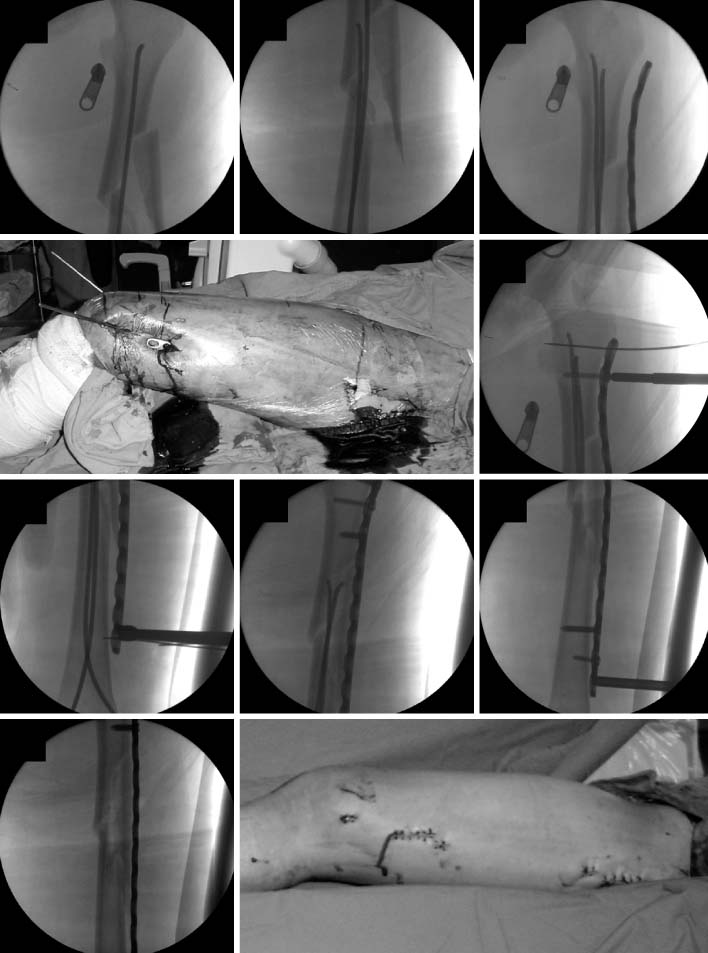

Fig. 6

In postoperative films (left), a satisfactory reduction was achieved. The patient had a solid union, on 1 year follow-up films (right).

Fig. 6 In postoperative films (left), a satisfactory reduction was achieved. The patient had a solid union, on 1 year follow-up films (right).